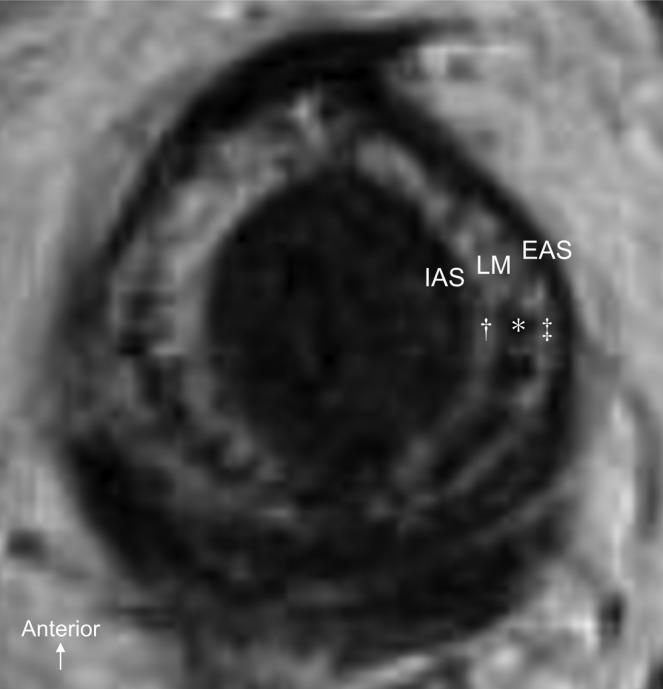

Magnetic resonance images of the anal canal show small, circular, low-intensity areas arranged in a row and a high-intensity area surrounding them internally and externally in the longitudinal muscle layer that cannot be explained by current anatomical findings. The purpose of this study was to elucidate the detailed structure of the longitudinal smooth muscle of the anal canal and to interpret the magnetic resonance image of the longitudinal muscle. Specimens for macroscopic anatomy and histology were obtained from six and seven cadavers, respectively. The histological nature of the longitudinal muscle was examined by staining serial transverse and coronal sections of the lateral wall of the anal canal with Masson's trichrome stain and using immunohistochemistry for smooth and skeletal muscle fibers. Dense and sparse areas of smooth muscle fibers coexisted in the longitudinal muscle layer. The dense areas formed columnar muscle bundles approximately 1.0-1.5 mm in diameter, and they continued from the longitudinal muscle bundles of the rectum. The columnar muscle bundles of the longitudinal anal muscle were internally and externally surrounded by sparsely arranged smooth muscle fibers that ran longitudinally. The coexistence of dense and sparse areas of smooth muscle fibers suggests that the structure of the smooth muscle is optimized for its function. This histological nature is probably reflected in the magnetic resonance image of the longitudinal muscle as the coexistence of low- and high-intensity areas. Clin. Anat. 33:619-626, 2020. © 2019 Wiley Periodicals, Inc.

肛管的磁共振成像显示,在纵向肌层中,排列成一行的小圆形低信号强度区域和环绕它们的高信号强度区域,这不能用当前的解剖学发现来解释。本研究的目的是阐明肛管纵向平滑肌的详细结构,并解释纵向肌的磁共振图像。分别从六个和七个尸体中获得了用于大体解剖和组织学的标本。通过对肛管外侧壁的连续横切和冠状切片进行 Masson 三色染色,并使用平滑肌和骨骼肌纤维的免疫组织化学染色,检查纵向肌的组织学性质。在纵向肌层中存在密集和稀疏的平滑肌纤维区。密集区形成直径约 1.0-1.5 毫米的柱状肌束,并从直肠的纵向肌束延伸而来。纵向肛提肌的柱状肌束被纵向排列的稀疏平滑肌纤维环绕。密集和稀疏的平滑肌纤维共存表明平滑肌的结构优化了其功能。这种组织学性质可能反映在纵向肌的磁共振图像中,表现为低信号强度和高信号强度区域的共存。临床解剖学 33:619-626, 2020. © 2019 Wiley Periodicals, Inc.